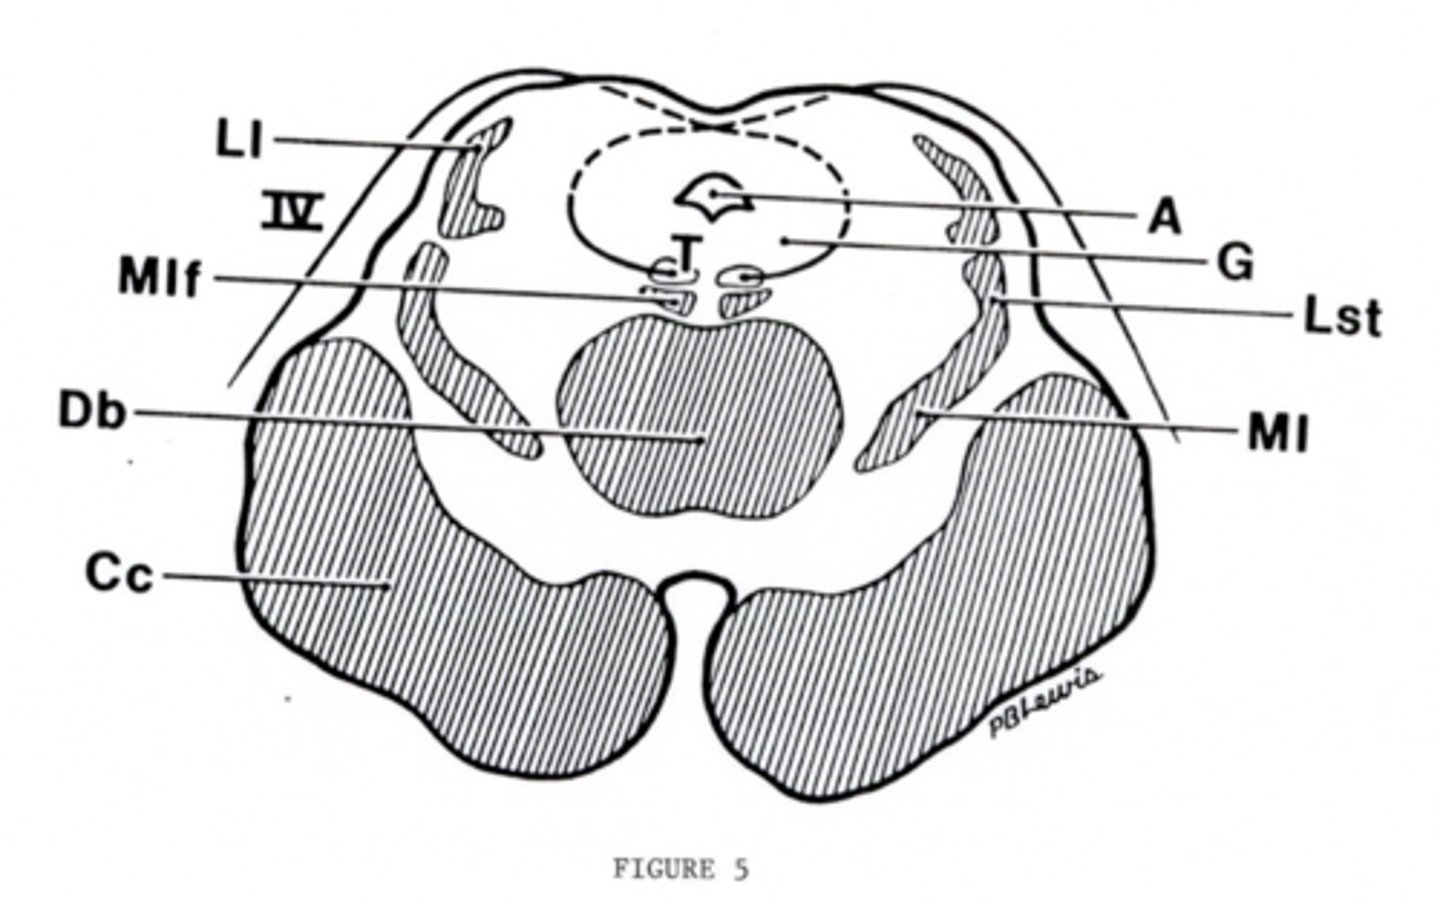

What is the floor of the 4th ventricle?

tegmentum pons

image -- green

What cranial nerve nuclei are in the tegmentum pons?

1. CN V (5)

2. CN VI (6)

3. CN VII (7)

4. CN VIII (8)